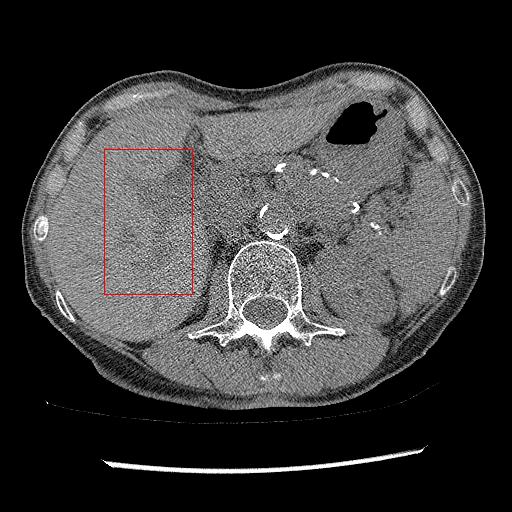

As shown in Table 3, DIP has exhibited the worst performance among all the methods. On the other hand, the ConsensusNet yielded a better FID and TML than BM3D but a lower PSNR and SSIM than other methods. The ConsensusNet divided the original projection data of the low dose CT image into two subgroups and back-projected to create the noisy input signal. Consequently, the noisy input image is much noisier than the original LDCT image. Also, the structural loss occurred during the generation of noisy images, so as a result, the PSNR and SSIM of this method are lower than other methods. Texture matching loss (TML) is used to measure the texture difference between the reconstructed and original images. The lower value of TML indicates that the generated texture is similar to the original. In comparison, FID estimates the distance between the distribution of the generated image and real images. A lower value of FID signifies the generated images are more similar to the original image. The current deep learning era demands a denoised image with a low value of these metrics. These denoised images may be used as input for other image classification tasks or segmentation networks. In this regard, the ConsensusNet is superior to the BM3D because it uses the deep neural network’s expression power. CycleGAN is another powerful unsupervised method for image-to-image translation; it achieved better performance than the other methods. However, CycleGAN has a lot of bottlenecks, e.g., longer training time, computation power, hyper-parameter tuning, etc. All these bottlenecks make CycleGAN ill-suited for practical deployment. Meanwhile, our proposed method has achieved the highest PSNR, SSIM, FID, and VIF among all the other methods. Next, we compare the result of denoising visually in Figure 6. It can be observed that the proposed method performs significantly better than the other unsupervised methods. BM3D output produced a blurry denoised image and contained many splotchy artifacts. The same blurriness can be observed in the output of ConsensusNet, and DIP, although noise suppression is adequate, and splotchy artifact is absent. In the output of CycleGAN, we can observe the presence of residual noise, especially in the high noise regions. Next, we identified one low attenuated lesion in the sample image and marked the lesion with a red colour bounding box. The zoomed view of the region inside the bounding box is given in Figure 7. In our method’s output image, the lesion’s visibility is enhanced significantly than in other methods. Despite being an unsupervised method, the visibility of the lesion is comparable with the original NDCT image. Also, from the zoomed view, we can perceive that our method has suppressed the granular pattern without losing the original image’s texture.

Figure 6: Result of denoising for comparison. We have shown an example of denoising performance on image taken from the 2016 NIH-AAPM-Mayo Clinic Grand Challenge dataset. The display window is [140140-140, 260] HU for better visualization of low attenuated lesion. Readers are requested to zoom in for better view.

Figure 7: Comparison of denoising performance of different network. Zoomed view of the region inside the bounding box shown in the images for Figure 6

Here, we analyse the performance of the proposed method on clinical data. Since there are no ground truths available, only qualitative comparisons are performed. An example of the denoising performance of the proposed method is given in Figure 8. Here we can see denoising performance of BM3D is the worst compared to other methods. On the other hand, the output of the deep image prior is very blurry, different organ boundary is distorted, and some splotchy artifacts appear in the image. The performance of DIP depends mainly on the stopping iteration; with more iterations, it will again produce the original noisy image. The clean image produced by it is always blurry and without any texture. Consistent with our previous example, we can see CycleGAN has a lot of residual noise left in the example. Next, we identified one hypodense lesion in the image and marked the region with the red colour bounding box. The zoomed version of the region containing the lesion is shown in Figure 9. The effect of denoising is perceptible in this zoomed view. The visibility of the lesion is very inconspicuous in the original LDCT image. The noise variance is very high in this region; consequently, BM3D and CycleGAN failed to remove noise from this region. On the other hand, DIP has removed the noise but also destroyed the image by removing all the texture information. ConsensusNet also produced a blurry version of the lesion in the output. At the same time, our method produced a denoised image with the lowest granular pattern and improved the lesion’s visibility. The main objective of image denoising is to restore the visibility of these types of lesions and anomalies by concealing the noise. In this regard, our method has reached the goal as the perceptibility of different anomalies has been improved vastly without losing structural or textural information.